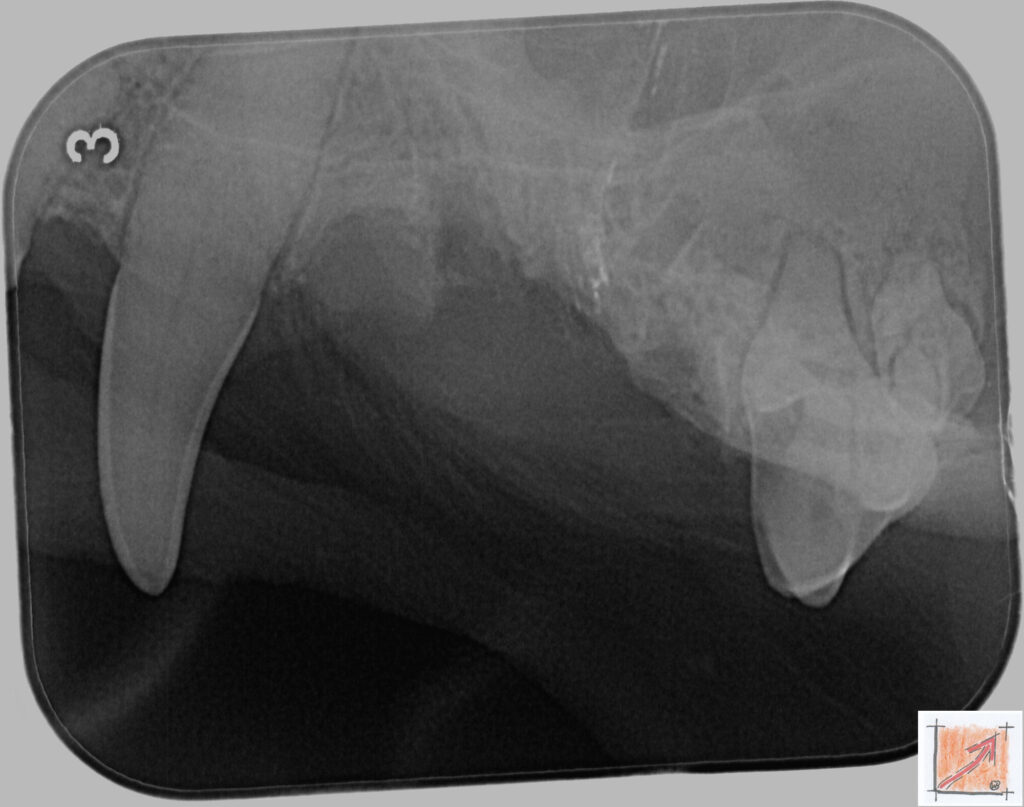

Röntgenbilder vom Thierrischen Orakel bei der Zahn-OP:

Warum Dentalröntgen beim Chihuahua lebenswichtig ist:

Ein Blick hinter die Kulissen von Chihuahua-Zähnen:

In dieser Galerie zeigen wir exklusive intraorale Röntgenaufnahmen einer Zahn-Operation beim Thierrischen Orakel als Chihuahua vom BauFachForum. Während oberflächlicher Zahnstein oft sichtbar ist, verbirgt sich die wahre Gefahr für das Herz meist unter dem Zahnfleischsaum.

Das digitale Dentalröntgen ist der Goldstandard in der modernen Tiermedizin, um parodontale Entzündungsherde und Wurzelabszesse sicher zu diagnostizieren. Für Chihuahuas wie dem Thierrischen Orakel, mit Mitralklappeninsuffizienz ist dieser diagnostische Schritt essenziell. Nur wenn versteckte Bakterienherde an der Zahnwurzel oder mit dem Fachbegriff Apikalabszesse erkannt und saniert werden, kann das Risiko einer bakteriellen Endokarditis oder einfach ausgedrückt einer Herzinnenhautentzündung minimiert werden.

Unsere Aufnahmen von Patienten dem Thierrischen Orakel verdeutlichen den Unterschied zwischen einer rein optischen Zahnreinigung und einer medizinisch fundierten Sanierung unter Röntgenkontrolle.

Chihuahua Mitralklappeninsuffizienz Trachealkollaps:

Wichtig ist im Vorfeld die Zahnhygiene des Chihuahuas. Die Bilder zeigen Dentale Röntgenbilder vom Thierrischen Orakel als Chihuahua-Hund während seiner Zahn-OP. Darstellung von Kieferknochen und Zahnwurzeln zur Diagnose von Parodontitis.

Zahnröntgenaufnahme bei Chihuahua Thierry:

Untersuchung der Zahnwurzeln auf Entzündungsherde als Prophylaxe gegen bakterielle Endokarditis.

Intraorales Dentalröntgen eines Chihuahuas:

Die Bilder zeigen Zähne und Wurzelstrukturen im Unterkiefer zur Planung einer Extraktion bei hochgradigem Zahnstein.